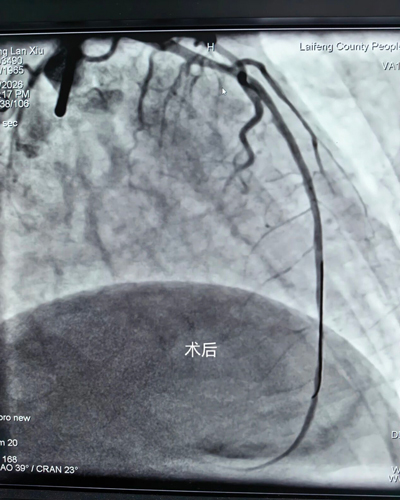

2026年2月22日,龙山县人民医院心内科接诊一名急性胸痛发病12小时患者,心电图诊断为急性广泛前壁心肌梗死,病情十分危重,需要紧急进行冠脉介入手术(PCI)开通血管抢救生命,恰巧导管室占台,龙山县人民医院心内科刘主任果断处理,紧急联系来凤县人民医院心内科朱兴彪主任,接到相关信息后,来凤县人民医院心内科团队立即启动“急性心肌梗死”救治流程及快速激活导管室,实行先诊疗后付费,绕行急诊科和CCU,全程绿色通道直达导管室进行急诊PCI术,手术D2B仅为26分钟,极大程度缩短抢救时间,挽救患者心肌。该患者于3月2日顺利康复出院,后期可在龙山县或来凤县进行门诊随访及治疗。